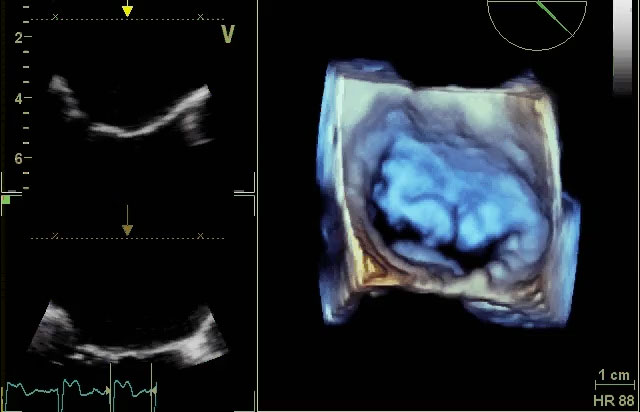

Impianto di Mitraclip: Monitoraggio ecocardiografico

Mauro Pepi